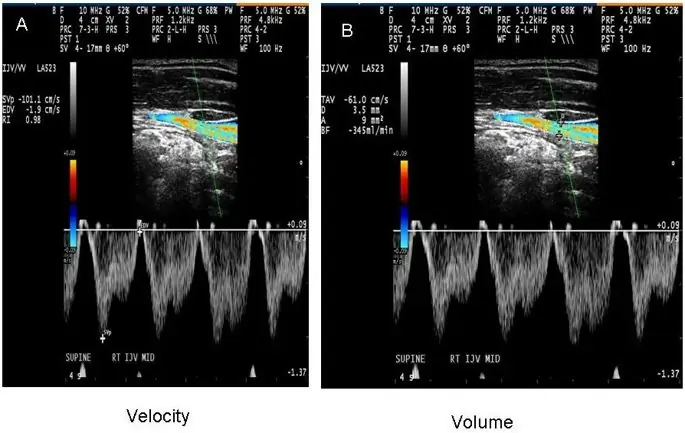

Из-за преимуществ DS в обнаружении внутрипросветной венозной патологии, он был первоначально продвинут в качестве метода выбора для скрининга экстракраниальных венозных аномалий и вариантов развития, показательных для CCSVI (18, 27). Диагноз CCSVI основан на результатах гемодинамики и визуализации, которые используют DS для изучения глубоких мозговых вен, IJV и позвоночных вен (VV) как в прямом, так и в положении лежа на спине. DS также может оценивать гемодинамические последствия нарушения оттока, в то время как ультразвук в B-режиме обнаруживает структурные венозные внутрипросветные аномалии (Figure 1E, F) (18, 27, 31, 33, 109, 112). Zamboni et al. создали набор из пяти критериев DS VH, по которым пациенты с MS отличались от здоровых контролей со 100% специфичностью и чувствительностью (18, 27) (рис. 1). Однако в своей первоначальной публикации (18) они не рекомендовали точные технические процедуры для применения протокола ни в исследовательских, ни в обычных клинических условиях. Первая попытка определить стандартизированный протокол сканирования CCSVI была недавно представлена (98). Совсем недавно Международное общество нейроваскулярных заболеваний (ISNVD) разработало более всеобъемлющий согласованный документ, в котором приняли участие более 40 международных экспертов в области визуализации DS. DS был предложен как стандартизированный инструмент скрининга для определения статуса CCSVI (33). Протокол предлагает использовать количественные измерения для определения функциональных аномалий, таких как скорость и объем кровотока (рис. 2), которые могут быть потенциально более надежными при оценке степени обструкции венозного оттока в IJVs. Он также уточняет первоначально предложенные критерии VH. Еще недавно Европейское общество нейросонологии и церебральной гемодинамики (ESNCH) выразило серьезные опасения относительно точности предложенных критериев для CCSVI при MS (32), и предложило центральное слепое чтение DS как часть недавнего многоцентрового итальянского CoSMo исследование, изучающее распространенность CCSVI у пациентов с РС, контрольной группы и пациентов с ОНД (113).

фигура 2

Пример измерения скорости (A) и объема (B) в течение четырехсекундной фазы во внутренней яремной вене (IJV)

Распространенность CCSVI и JVR, а также их связь с клиническими данными при нарушениях ЦНС подчеркивают необходимость более количественных и воспроизводимых мер для интеграции морфологических и функциональных аномалий. К ним относятся кровоток, а также скорость и объем крови, которые могут быть потенциально более надежными при оценке степени обструкции венозного оттока в IJVs и азиготной вене (рис. 2). Экзамены с контрастным усилением потенциально могут увеличить значение DS (90). Как сообщалось недавно, существует потребность в обучении и использовании стандартизированных критериев VH для диагностики CCSVI (33, 98). Хотя значение этих критериев VH при обнаружении венозных аномалий или вариантов развития является неопределенным (32), в настоящее время не было предложено никаких других подтвержденных критериев. Мы надеемся, что быстро растущая литература будет способствовать совершенствованию протоколов и процедур, которые будут использоваться при исследовании внечерепной венозной системы (113).